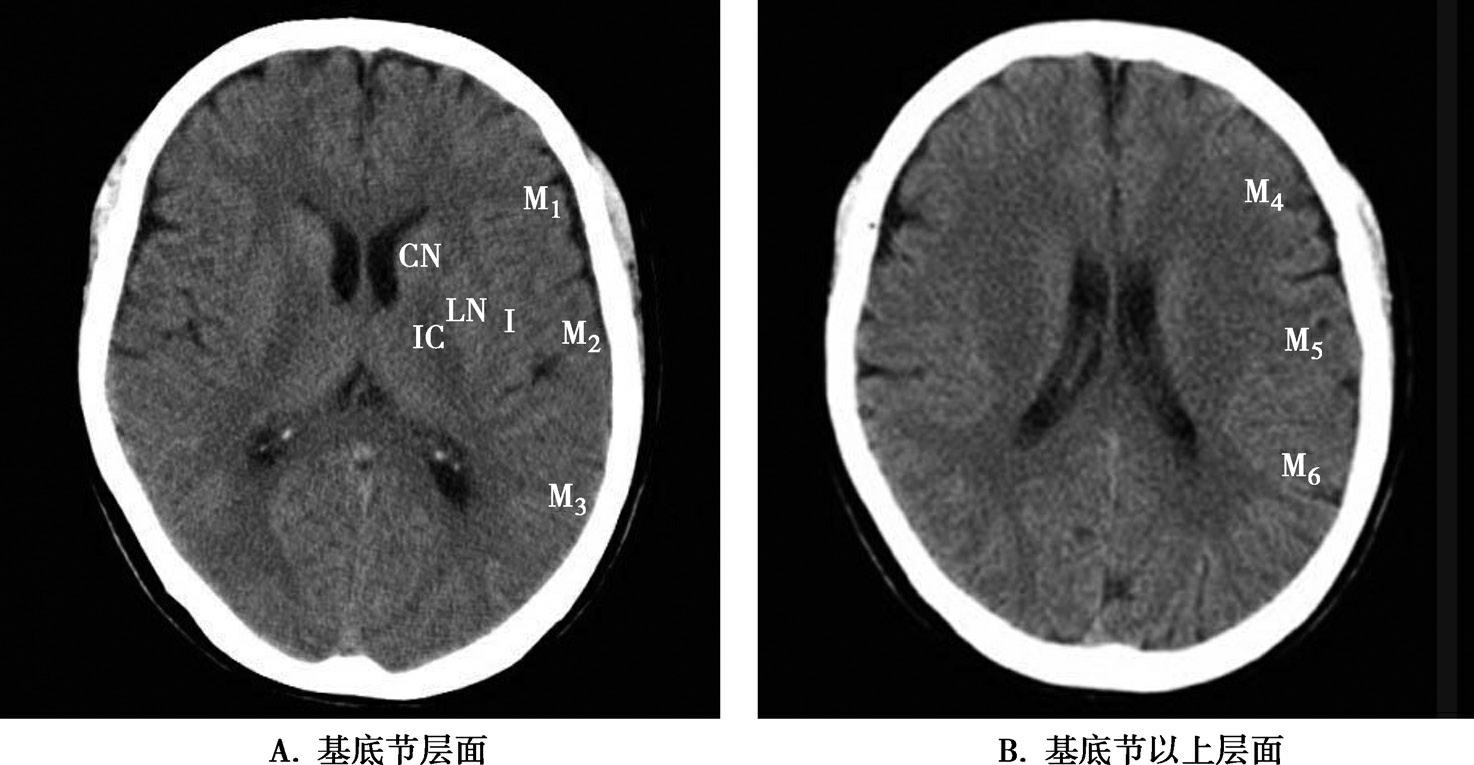

基底节为脑卒中的好发部位,与纹状动脉的解剖特点有关,深穿支动脉的破裂和栓塞可分别引起基底节区的出血和梗死(图1-2-32、图1-2-33)。

图1-2-32 脑出血

A.右侧壳核脑出血,形成高密度血肿(★);B.右侧丘脑出血,呈球形高密度影(箭)

图1-2-33 基底节区脑梗死

A.右侧丘脑梗死,病灶呈圆形低密度影(箭);B.左侧内囊膝部及后肢梗死,呈带状低密度影(箭)